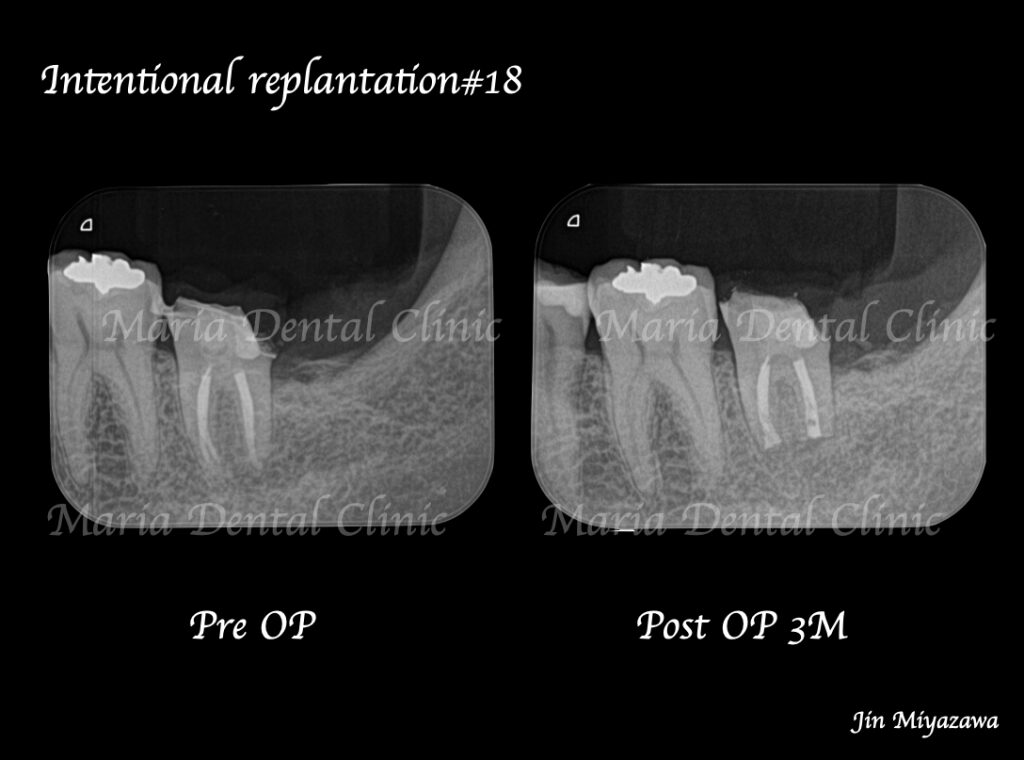

今回のような最後方臼歯(一番後ろの歯)に対しては、解剖学的に骨の厚みや器具の到達を考え、意図的再植術を適応させることになります。

違和感や痛みは術後1ヶ月程で消失し、3ヶ月後には術直後に見られていた左下7番根尖部に確認できた透過像も消失し、順調に骨が作られていることが確認できます。

今後、最終補綴に移行し、1年後の経過観察を行う予定です。